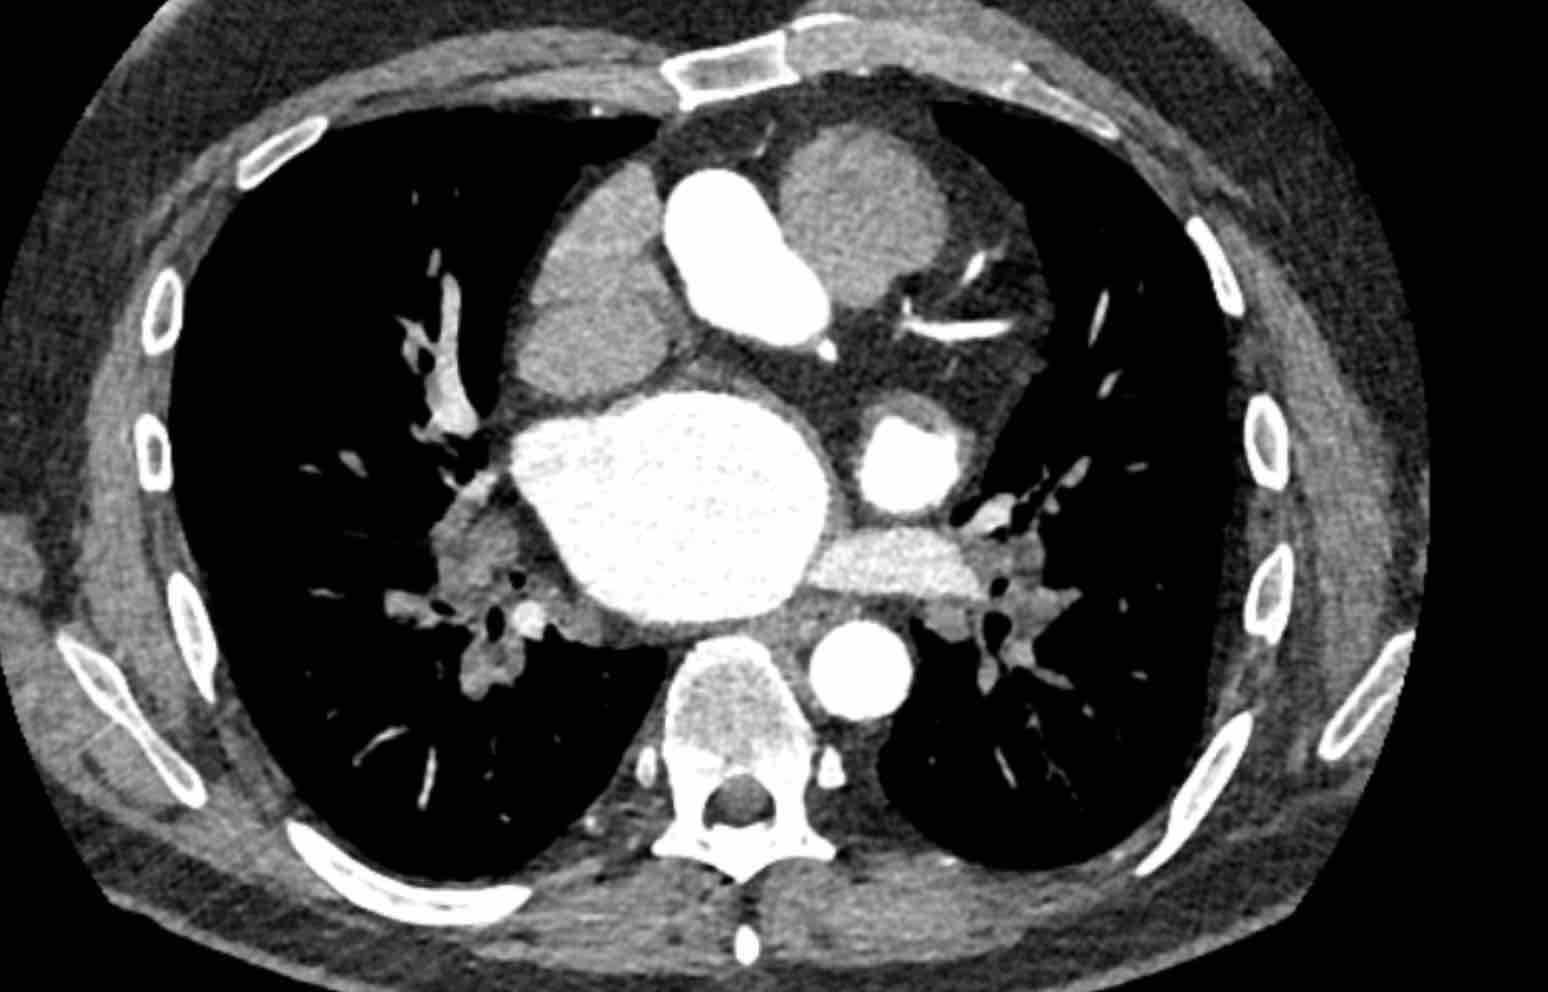

Hình ảnh

Phì đại động mạch phế quản với đường kính lên đến 4 mm (mũi tên) kèm theo một túi phình nhỏ (đầu mũi tên).